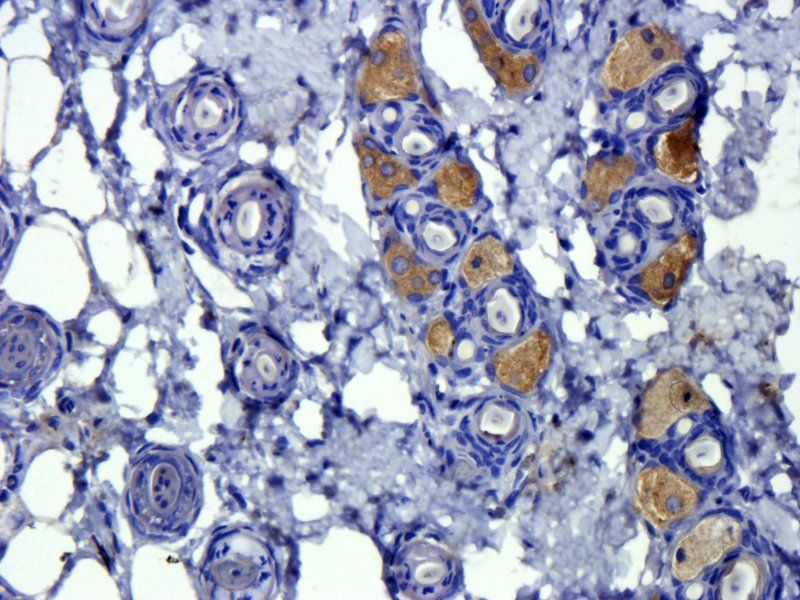

Rat kidney cells expressing TGF beta 1 (IHC-p with DAB as chromogen)